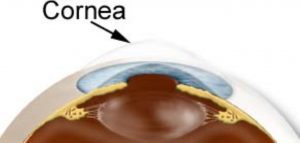

Gözümüzdeki kornea tabakasının konveksliğinin (Öne doğru eğim) düzensiz ve kontrolsüz şekilde artmasına KERATOKONUS denir. Kornea dokusunun konveksliği artarken kırma gücü ve astigmatizma da artar ve kornea incelir. Oluşan astigmatizma düzensiz olduğu için gözlük ile tam olarak düzeltilemez ve gözlük numarası sürekli değişir.

Gözümüzün en ön parçasını oluşturan ve net görmemizde önemli katkı sağlayan kornea dokusunun 7-9 mm’lik bir kısmının çıkartılarak yerine aynı çaptaki donör korneasının dikilmesi işlemine keratoplasti (Kornea nakli) denir.